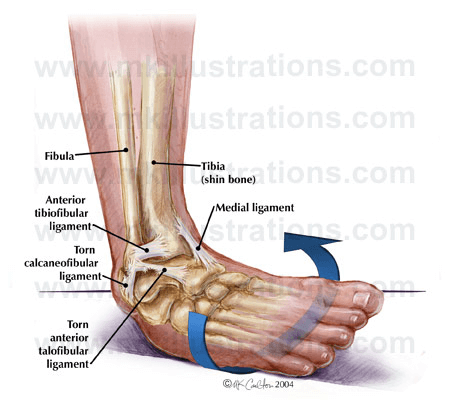

Ankle and foot